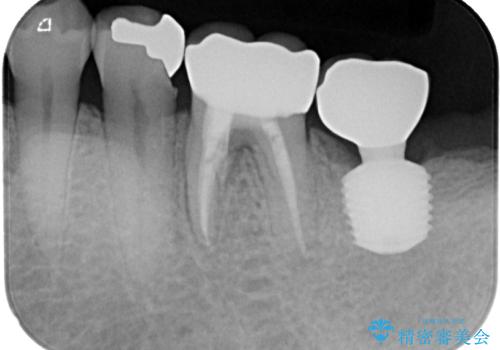

- 以前、咬合力の強さで歯の神経が失活してしまい、当院にて根管治療を行った患者様ですが、今度は咬合力の影響で歯根が破折してしまった患者様です。

歯根が破折してしまった歯は抜歯が必要となり、特に咬合力が強い方ですと、インプラント治療による治療がお勧めとなります。

従来のインプラント治療ですと、抜歯をしてからその部分の骨が回復するまで数か月待機し、その後インプラント埋入、生着を待って土台の頭出し手術、仮歯の装着となるため、咬合回復するまでに半年かそれ以上の期間が必要となってしまいます。

咬合力の影響で歯が壊れてしまう方の場合、長期間欠損が続くと、連鎖するように他の歯が壊されてしまうリスクがあるため、抜歯即時インプラントにより、治療期間の短縮を図ることとしました。